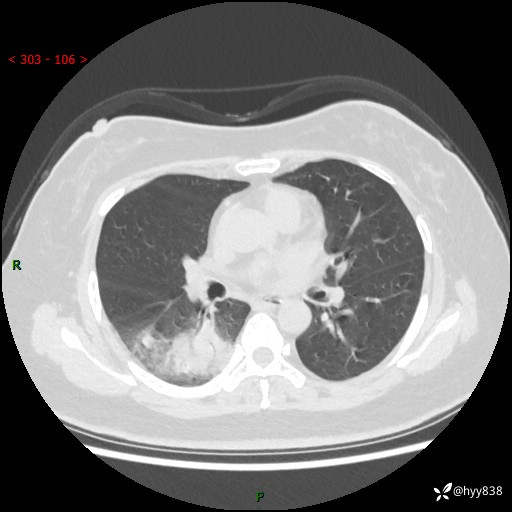

大叶性肺炎的表现形式,晒晒鉴别诊断吧…结果公布~

简要病史:患者8天前无明显诱因出现咳嗽、咳痰,为绿色脓痰,无明显加重与缓解因素,无高热、寒战,无呼吸困难,无大量脓痰,无哮鸣音,于当地医院行胸片示右下肺团块影,性质待定,予口服药物治疗症状未见明显改善,具体药名不详,为求进一步诊治来我院就诊,门诊以“肺占位性病变”收入我科进一步诊治。 患者自发病以来,精神、饮食尚可,睡眠欠佳,大小便正常,体力、体重未见明显异常。

辅助检查:CT

临床诊断:肺占位

胸部CT平扫